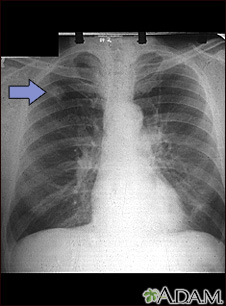

A chest x-ray is an x-ray of the chest, lungs, heart, large arteries, ribs, and diaphragm.

Images